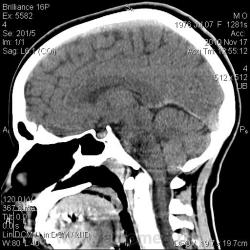

Тип патологии:

Область исследования:

Методы исследования:

- https://radiomed.ru/sites/default/files/styles/case_slider_image/public/user/2841/arnolda-kiari_1_st0005.jpg?itok=jhEApMjZ